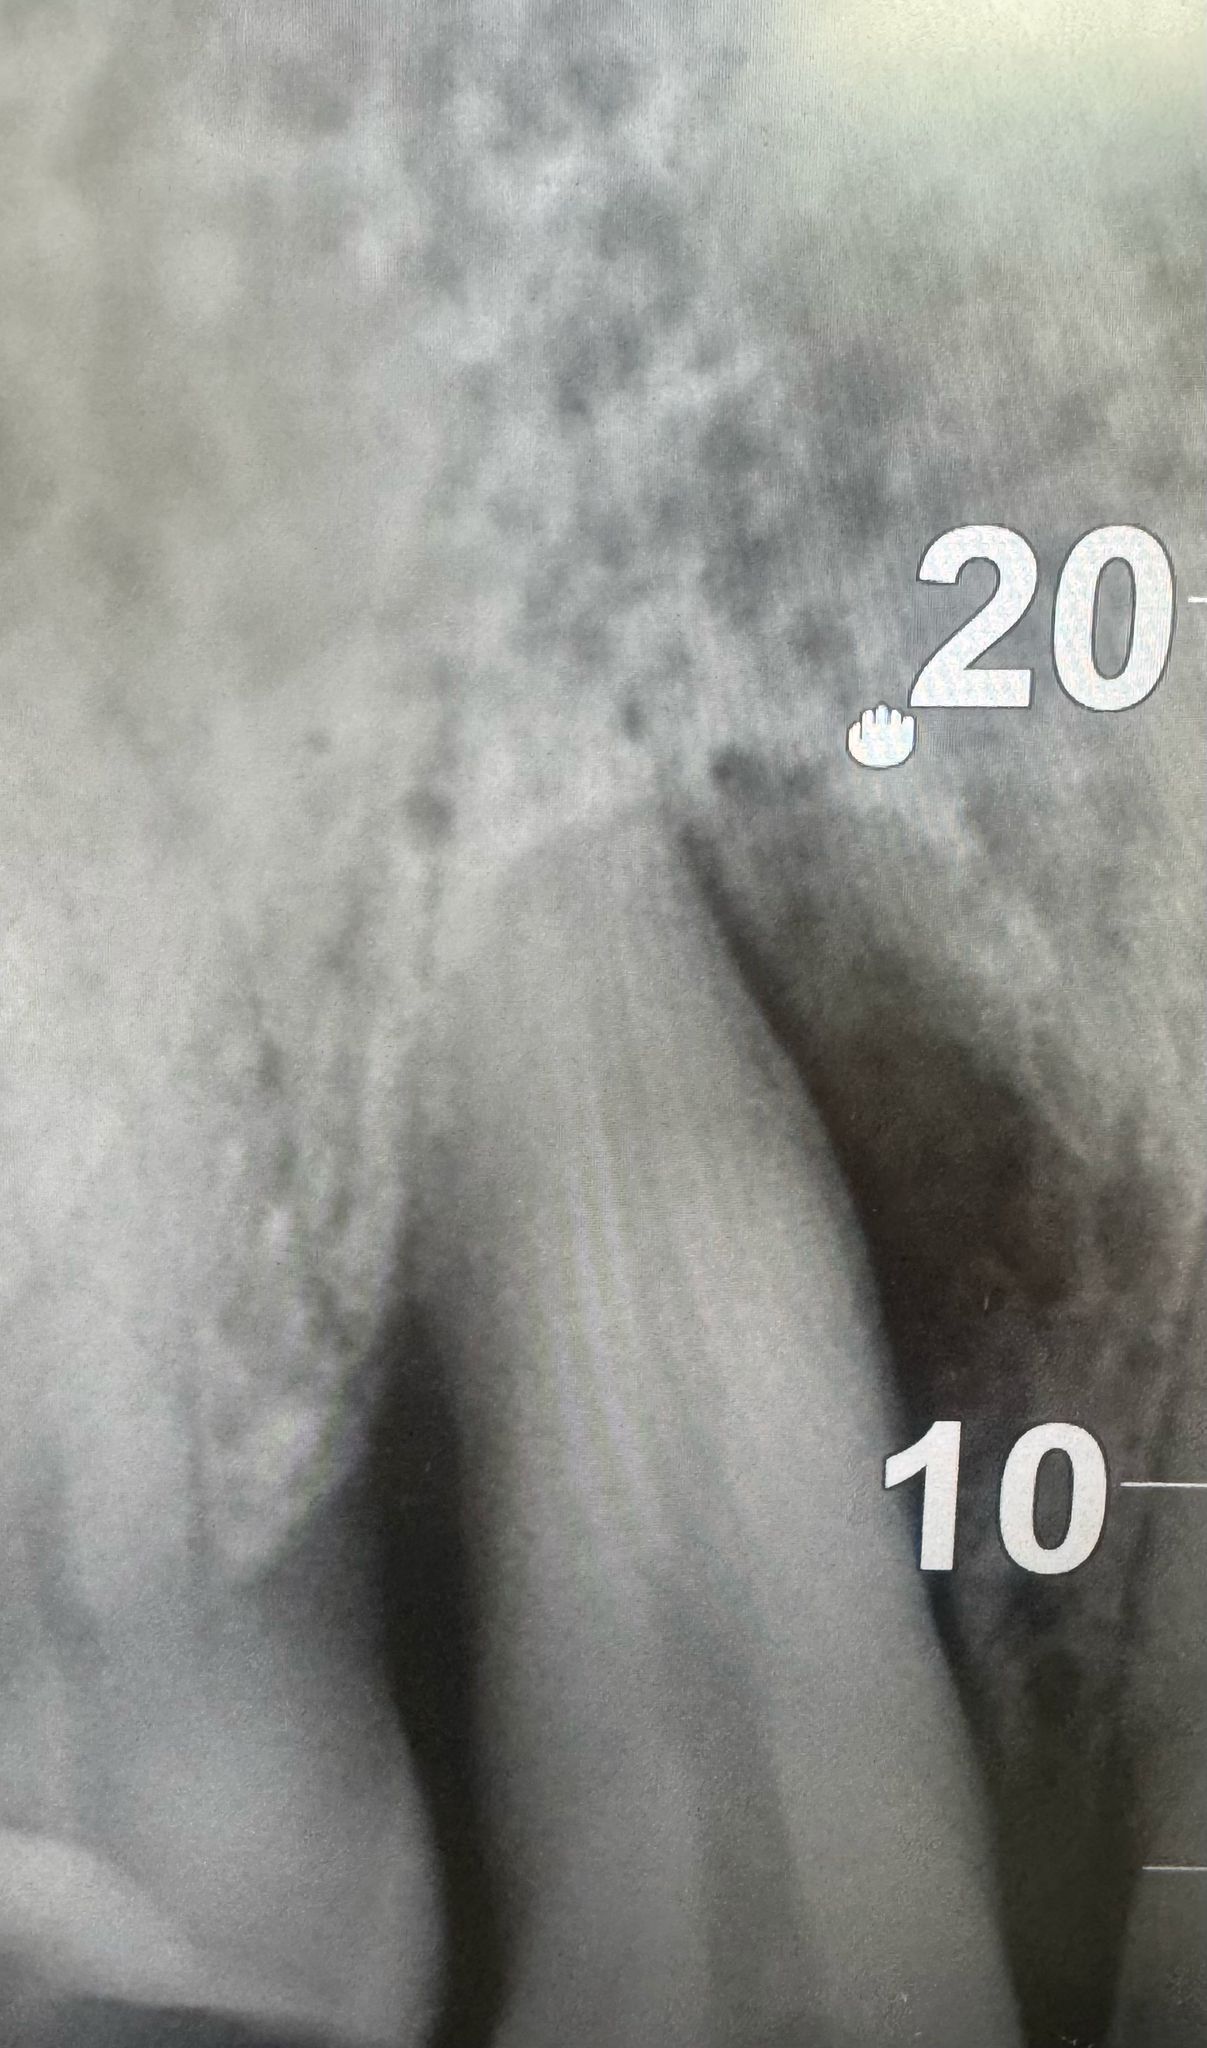

E' una procedura chirurgica che ha lo scopo di ricostruire (immagina 2) il volume osseo mancante e/o insufficiente (immagine 1), in alcune zone dell'osso alveolare dell'arcata dentale. Permette, dopo la rigenerativa dell'osso, di posizionare un impianto dentale (immagine 3) o di eliminare una tasca ossea adiacente ad un elemento dentale.